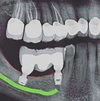

الصور